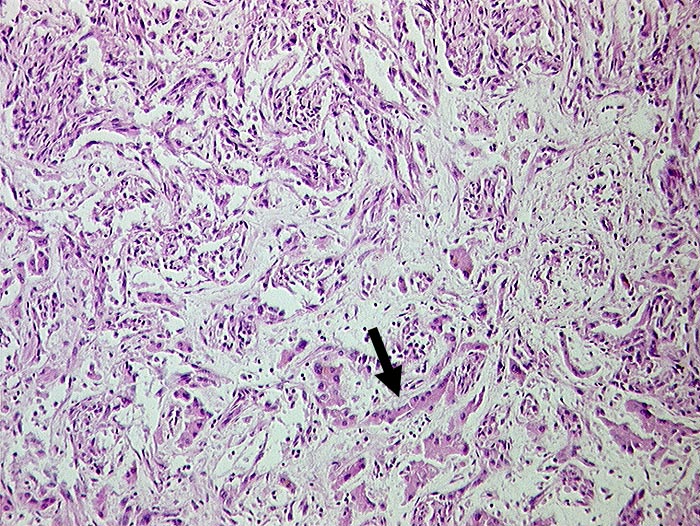

Angiosarkom der Leber

Pathologischer Befund